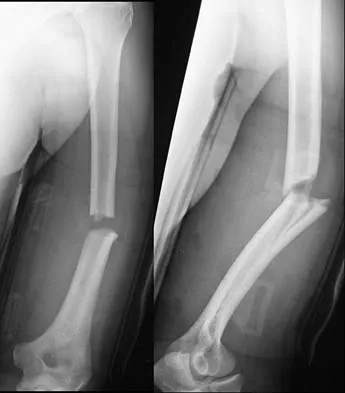

An 8-year-old boy sustains nondisplaced midshaft fractures of the tibia and fibula after being struck by a car while he was riding his bicycle. No other injuries are noted, but the patient reports pain with passive motion of his toes. His neurovascular examination is otherwise normal. What is the best course of action?

Explanation

Pain with passive motion of the toes is a recognized early sign of increased compartment pressures. At a minimum, a baseline evaluation of the leg compartment pressures should be obtained. While it is normal for the patient to have pain related to the associated muscle contusions, any significant concerns should be addressed immediately in light of the severe consequences likely when a compartment syndrome occurs. Mubarak SJ, Owen CA, Hargens AR, et al: Acute compartment syndromes: Diagnosis and treatment with the aid of the wick catheter. J Bone Joint Surg Am 1978;60:1091-1095.